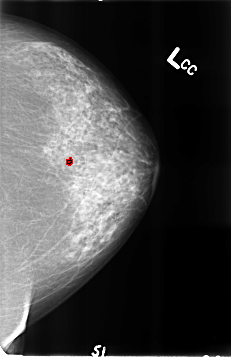

B_3220_1.LEFT_CC

LEFT_CC LINES 4632 PIXELS_PER_LINE 2992 BITS_PER_PIXEL 12 RESOLUTION 50 OVERLAY

FILE: B_3220_1.LEFT_CC.OVERLAY

TOTAL_ABNORMALITIES 1

ABNORMALITY 1

LESION_TYPE CALCIFICATION TYPE COARSE-ROUND_AND_REGULAR DISTRIBUTION N/A

ASSESSMENT 2

SUBTLETY 5

PATHOLOGY BENIGN_WITHOUT_CALLBACK

TOTAL_OUTLINES 1

BOUNDARY